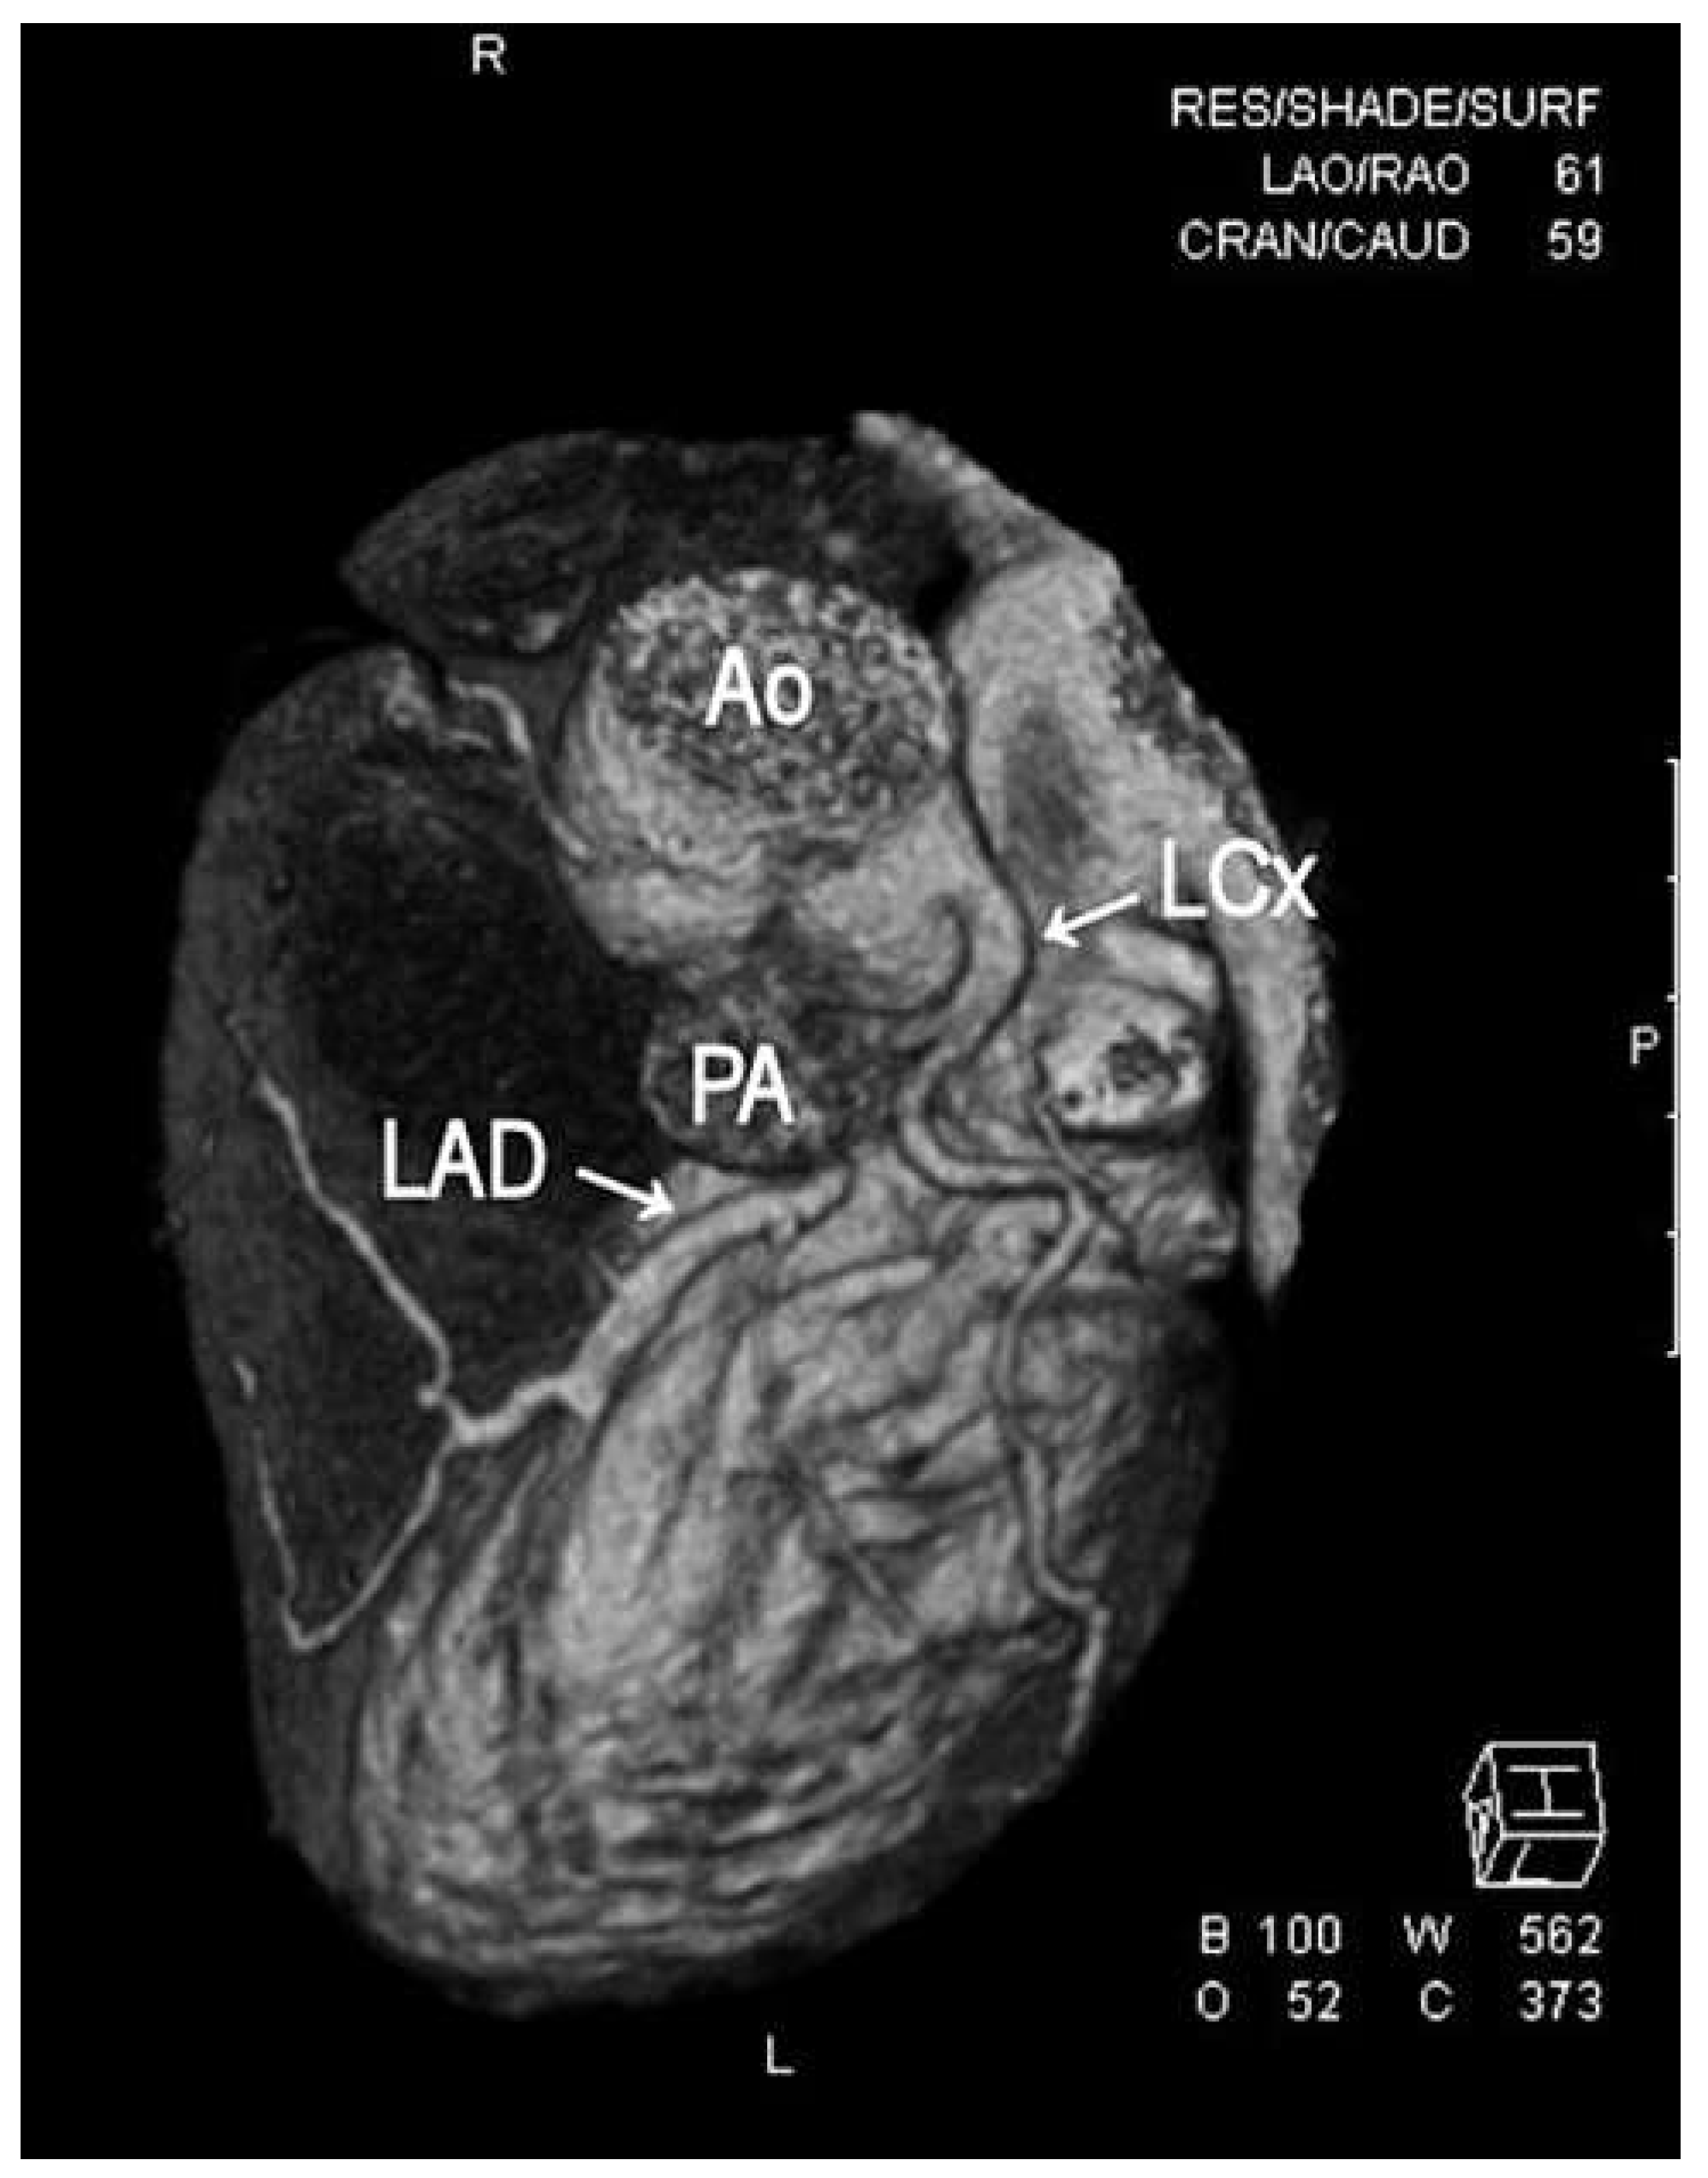

1. Case Report